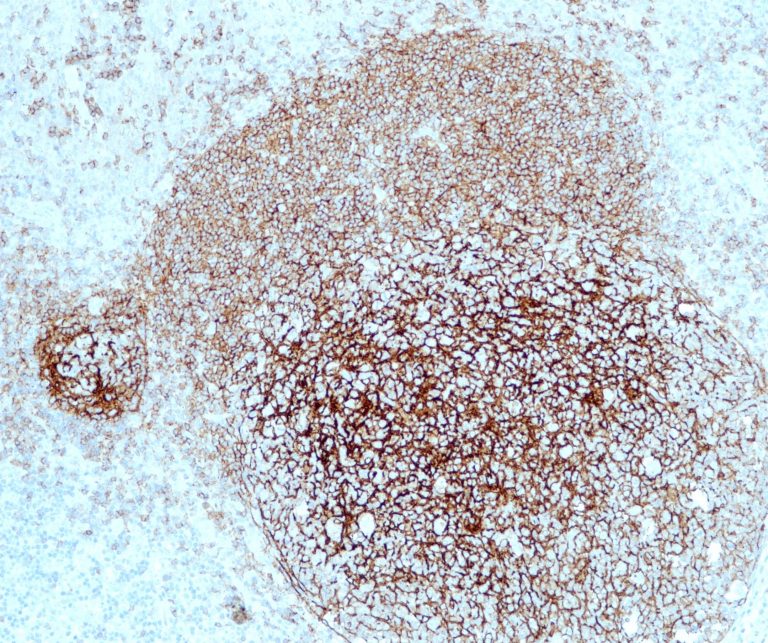

Vascular Pathology

Gastrointestinal (GI) Pathology

General Marker

Breast Pathology

Endocrine Pathology

Gynecological Pathology

Neuropathology

Infection Markers

Lung Pathology

Urinary Tract Pathology

Transplantation Pathology

Soft Tissue Pathology

Hematopathology